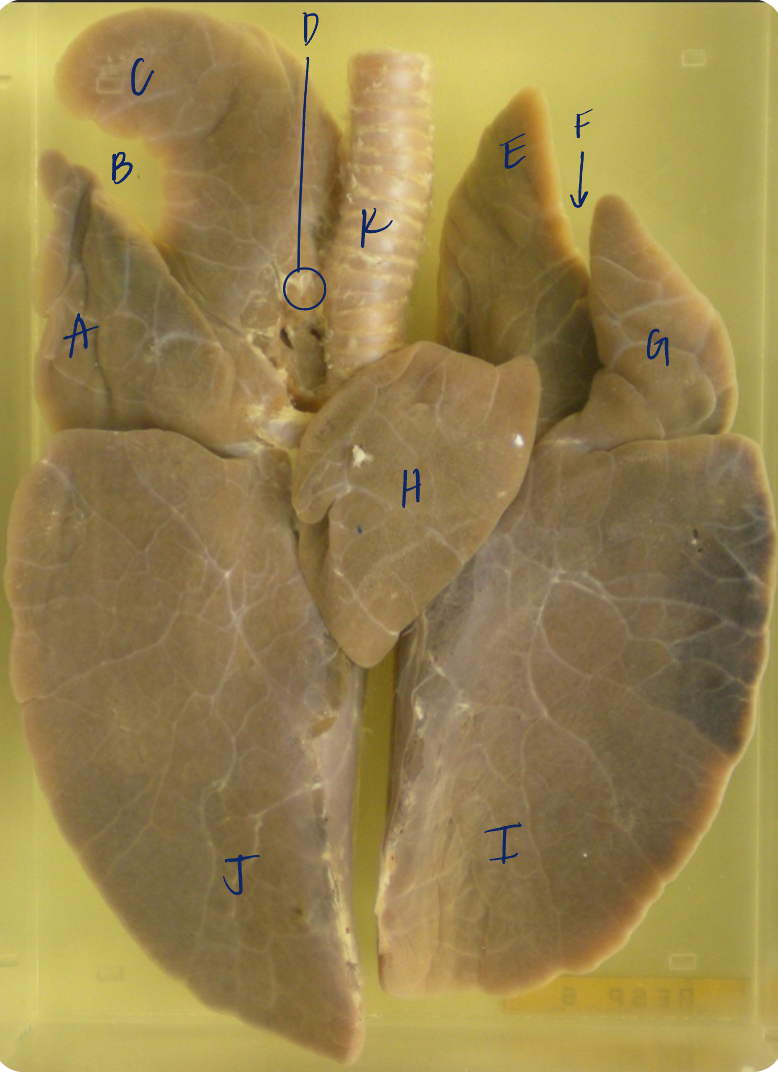

A

(dog lungs, dorsal)

L cranial lobe

B

(dog lungs, dorsal)

cranial segment, L cranial lobe

C

(dog lungs, dorsal)

caudal segment, L cranial lobe

D

(dog lungs, dorsal)

apex

E

(dog lungs, dorsal)

trachea

F

(dog lungs, dorsal)

R cranial lobe

G

(dog lungs, dorsal)

middle lobe

H

(dog lungs, dorsal)

R caudal lobe

I

(dog lungs, dorsal)

accessory lobe

J

(dog lungs, dorsal)

L caudal lobe